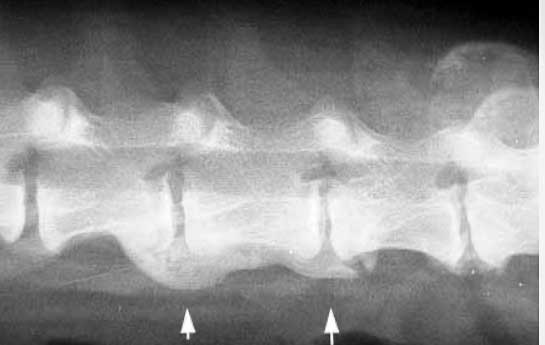

Disc Disease

The arrows are pointing to the lumbar spine of a dog with spondylosis, causing symptoms of arthritis